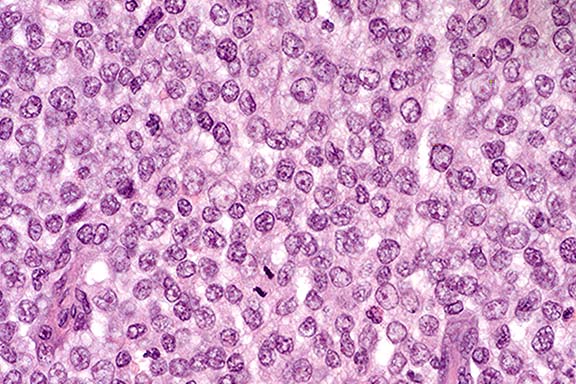

Histologically, the cells are round, ovoid or polyhedral and may be arranged in compact sheets. The cells contain moderate eosinophilic cytoplasm; nuclei have marginal chromatin and few mitotic figures. Differential diagnosis for this neoplastic mass includes lipoma, mast cell tumor, epidermoid carcinoma, squamous cell carcinoma, fibroma, and histiocytoma.

Case 17-1. Vulva. Note the compact sheet of round, oval, and occasionally irregular neoplastic cells with marginated chromatin and open to vesicular nuclei with a single mitotic figure. The scant to moderate cytoplasm is pale, foamy, and has indistinct membranes. 40X

AFIP Diagnosis: Vulvar mass: Transmissible venereal tumor, mixed breed, canine.